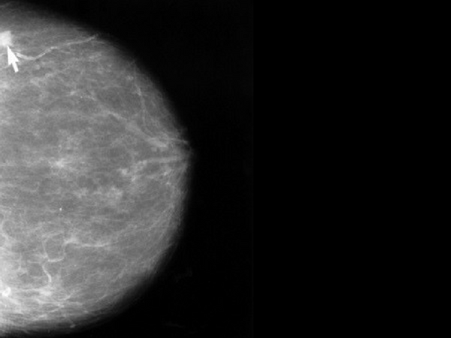

High Risk Group #7: Having Dense Breasts

The density of your breasts is a factor observable only under a mammogram. This is because on the outside all breasts feel alike.

It's only when you scan them that it is revealed whether they are mostly made of fat tissue (breast lobules and glands) or mostly made of connective tissue (the supporting tissues that hold everything together).

And if your breasts have more of the latter, then it is a problem because the dense structures prevent lumps or tumors from showing up on the scan.

2. Get mammograms done once every year after the age of 30.